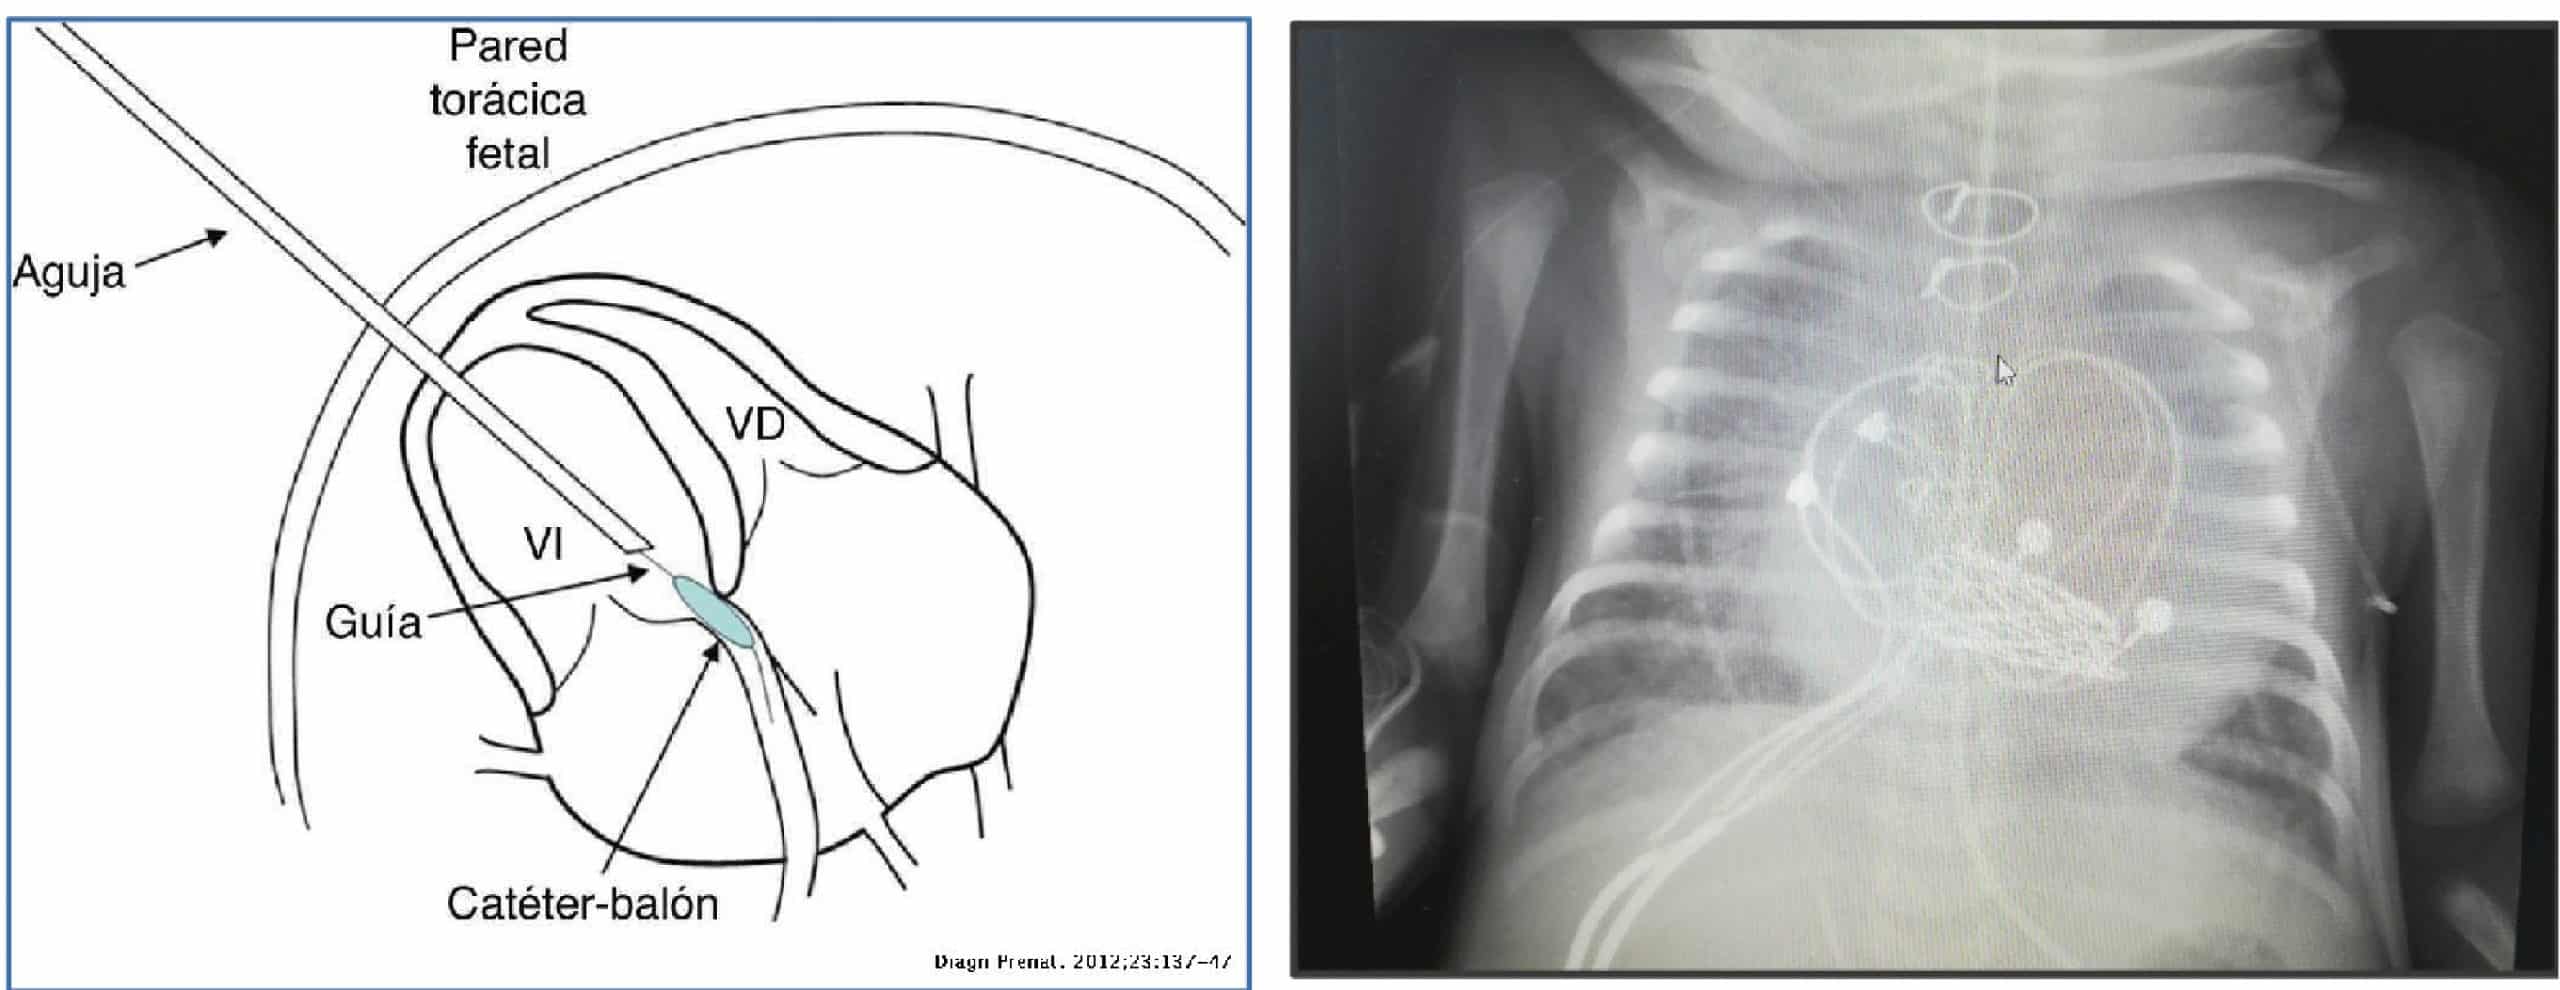

El caso que expone la doctora Victoria Ramos es el de un paciente con diagnóstico prenatal de estenosis aortica congénita grave, estenosis e insuficiencia mitral grave y fibroelastosis subendocárdica del ventrículo izquierdo, a pesar de que este, tenía un volumen adecuado.

- Se realizo una valvuloplastia fetal, con el fin de que se pudiera desarrollar la aorta ascendente, en la semana 23 de gestación, consiguiéndose una apertura de la válvula aortica de 3 mm.

- Al nacimiento, el paciente pesó 2,8 kg. y se iniciaron prostaglandinas E1. Con todos los datos del volumen del ventrículo y debido a su estenosis e insuficiencia mitral, se planificó una cirugía biventricular.

- Al séptimo día de vida, se realizó la cirugía cardiaca, cirugía de Ross-Konno.

Cirugía de Ross-Konno

La cirugía de Ross-Konno permite reparar la válvula aórtica dañada. Para ello, se utiliza la válvula pulmonar en posición aortica con translocación de las coronarias y en posición pulmonar se colocó un conducto contegra.

Además, debido a la doble lesión mitral con insuficiencia grave, también se colocó una válvula Melody® en posición mitral; y se realizó una resección de fibroelastosis.